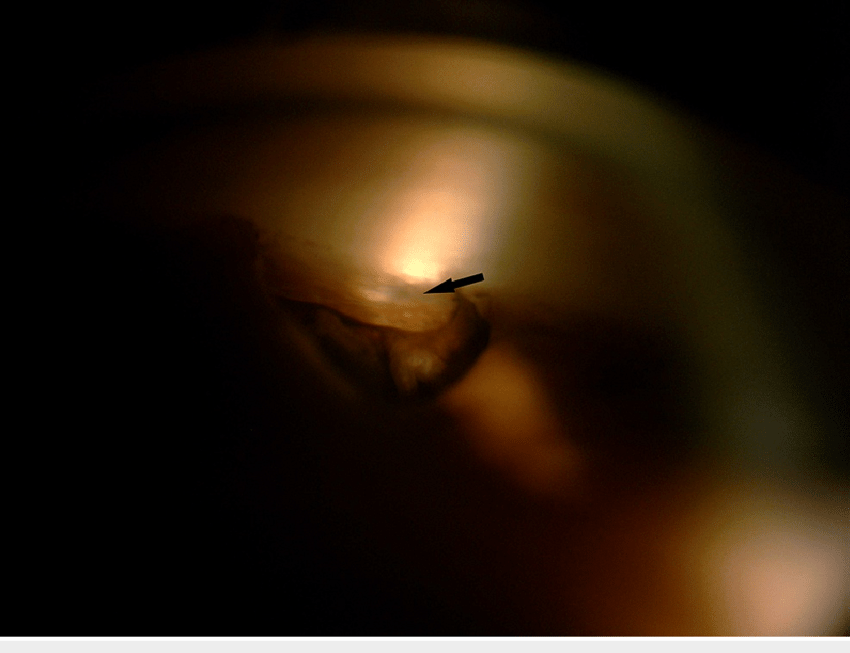

<여과포에서의 방수 누출, Leaking bleb>

1. 여과포에서부터 누출이 있으나, 전방의 깊이가 충분히 깊게 유지되며, 여과포에 염증이 없이 창백하면서 융기되어 있는 경우

우선 보존적으로 치료해볼수 있습니다.

대부분 안검의 운동에 의해서 스치면서 여과포에서 누출이 되기 때문에,

안검 운동을 막기위해서 연고를 넣고 압박 안대를 하면서 며칠간 지켜볼수 있습니다.